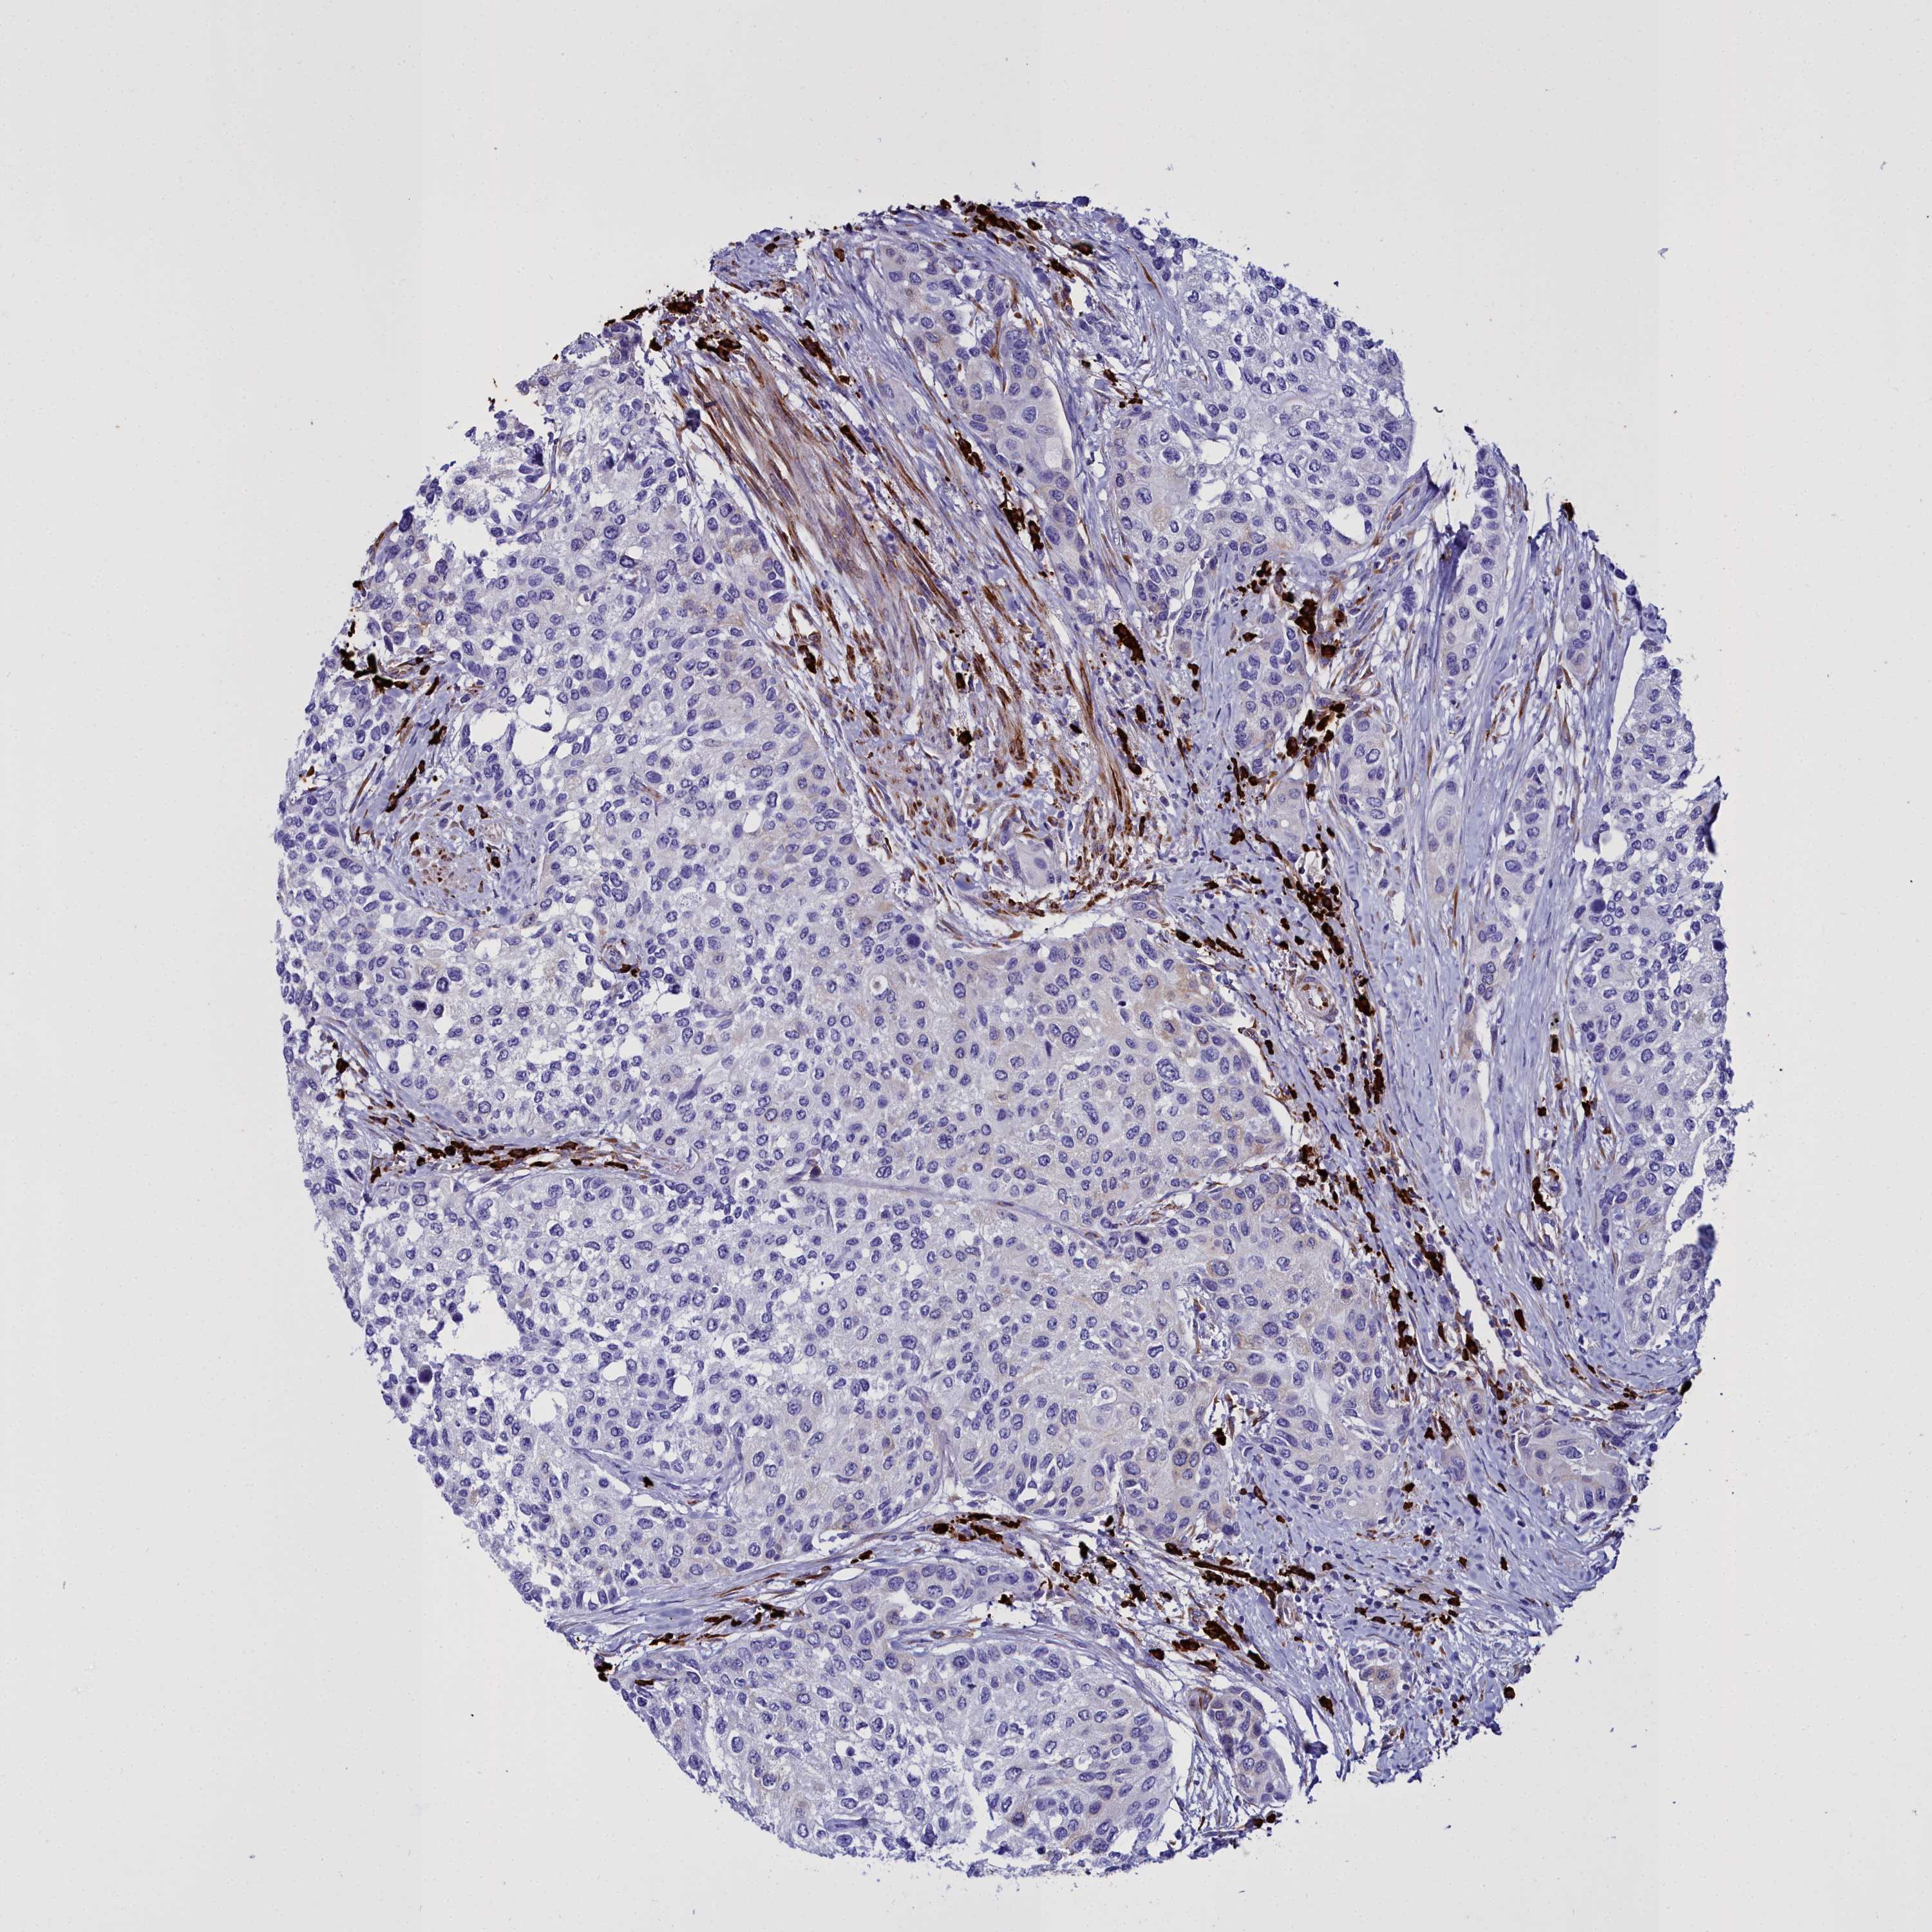

UROTHELIAL CANCER - Protein expressioni

A mouse-over function shows sample information and annotation data. Click on an image to view it in a full screen mode. Samples can be filtered based on level of antibody staining by selecting one or several of the following categories: high, medium, low and not detected. The assay and annotation is described here.

Note that samples used for immunohistochemistry by the Human Protein Atlas do not correspond to samples in the TCGA dataset.

Antibody stainingi

Antibody staining in the annotated cell types in the current human tissue is reported as not detected, low, medium, or high, based on conventional immunohistochemistry profiling in selected tissues. This score is based on the combination of the staining intensity and fraction of stained cells.

Each image is clickable and will lead to virtual microscopy that enables deeper exploration of all samples and also displays staining intensity scores, fraction scores and subcellular localization as well as patient and tissue information for each sample.

Antibody HPA034677

Antibody HPA034678

Staining

High

Medium

Low

Not detected

Intensity

Strong

Moderate

Weak

Negative

Quantity

>75%

75%-25%

<25%

None

Location

Nuclear

Cytoplasmic/membranous

Cytoplasmic/membranous,nuclear

Urothelial carcinoma, High grade

Urothelial carcinoma, Low grade